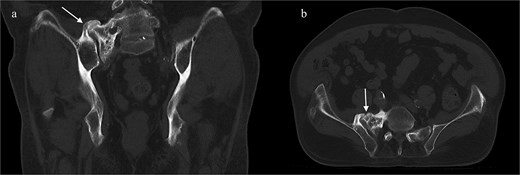

A CT of the pelvis showed significant hyperostosis along the anterior right SI joint and a pseudoarthrosis between the L5 transverse process and the sacral ala that was osteoblastic-appearing in nature (Fig. 1). A SPECT-CT demonstrated increased uptake along the same area, suggestive of inflammatory degenerative changes (Fig. 2).

Coronal (left) and axial (right) views of pelvic CT-SPECT highlighted increased uptake along the right SI joint, suggestive of inflammation (arrows).